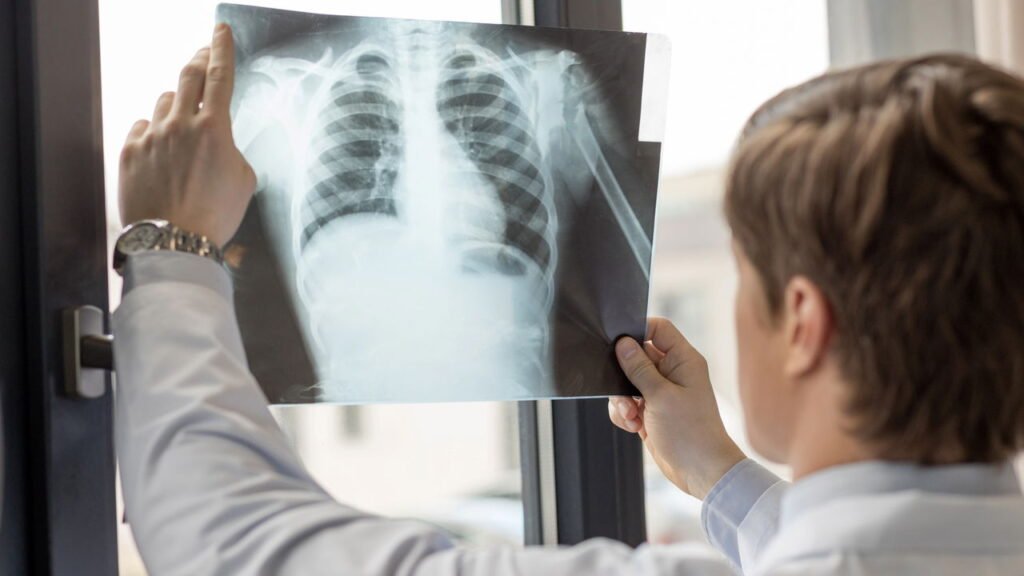

Como um erro gerou o desenvolvimento do raio-X?

O ano de 1895 marcou a descoberta dos raios-X, uma das ferramentas mais valiosas na medicina diagnóstica. O físico Wilhelm Röntgen estava experimentando com tubos de raios catódicos quando notou um brilho fluorescente em um material próximo ao tubo. Intrigado, ele começou a investigar essa emissão desconhecida.

Röntgen logo percebeu que os raios-X eram capazes de atravessar diversos materiais, incluindo tecidos humanos, mas não ossos, gerando imagens detalhadas do esqueleto. Este achado inesperado proporcionou uma ferramenta poderosa para diagnósticos médicos sem a necessidade de invasão ou cirurgia, revolucionando a medicina desde então. Hoje, as técnicas derivadas dos raios-X continuam a se aprimorar, sendo fundamentais também em áreas como segurança e pesquisa científica.